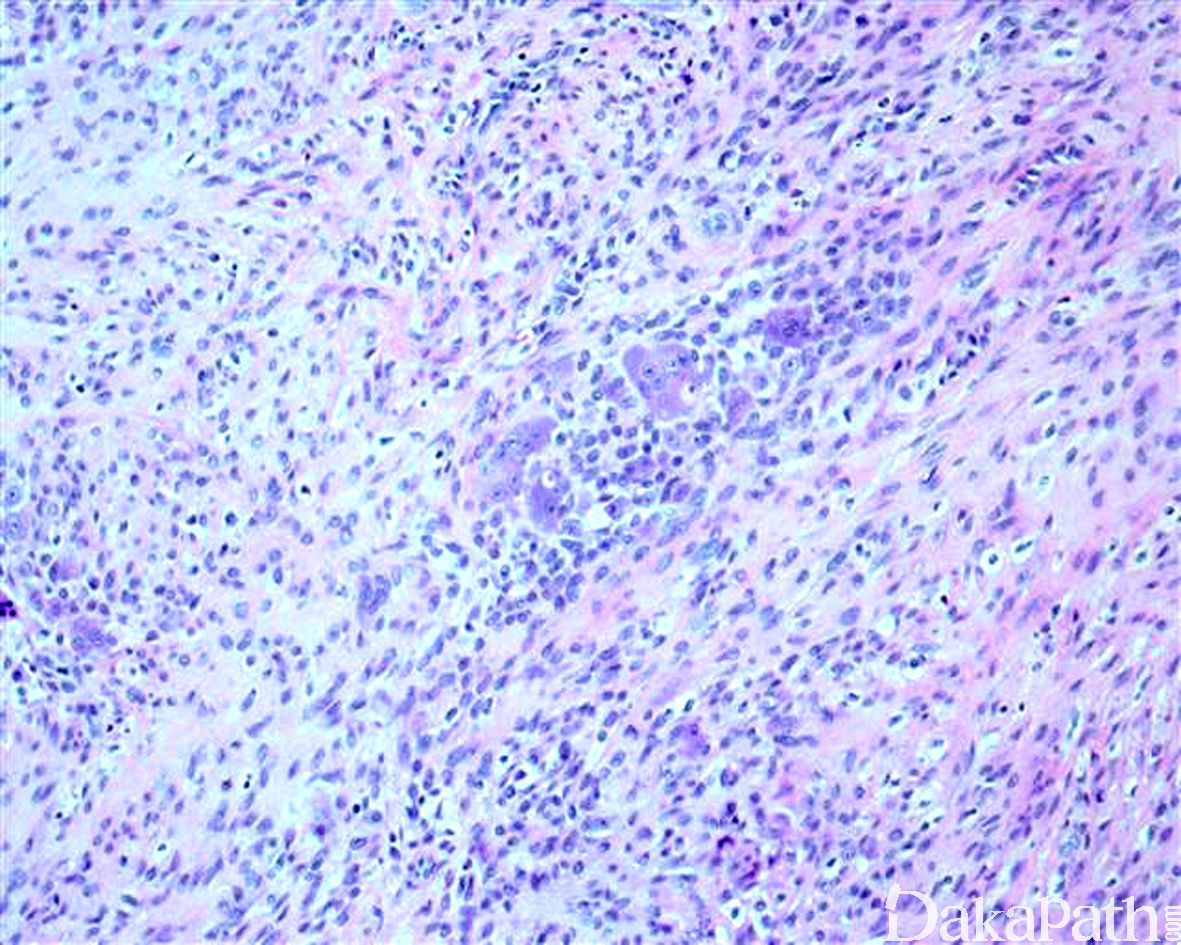

- 由胖梭形细胞栅栏状围绕软骨或点状钙化灶周围为其特征性改变;部分病例表现为梭形纤维母细胞浸 润性生长,细胞之间可见丰富的胶原纤维,两种结构可同时存在;

- 细胞胞质多少不等,界限不清,核卵圆形,染色质泡状,可聚集核膜下;

- 分裂像少见,无病理性核分裂像;

- 幼儿患者可富于细胞;